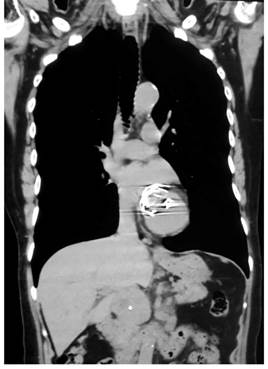

Se consideró inicialmente que la paciente se encuentra cursando con GIST gástrico ulcerado en el cuerpo gástrico distal sin sangrado activo y se complementó el estudio para evaluar el compromiso locorregional con la realización de tomografía axial computarizada (TAC) de abdomen y pelvis con hallazgos de masa del estroma gastrointestinal en el espacio gastrocólico compatible con un tumor de GIST (Figura 1) y masa o adenomegalia retroperitoneal por detrás de la cabeza de páncreas (Figura 2).